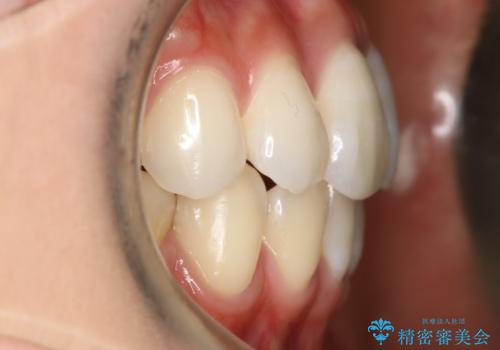

- ワイヤー(片顎舌側装置)

ハーフリンガル装置

ハーフリンガルとは上顎を裏側、下顎を表側のワイヤー装置で治療する場合をいいます。